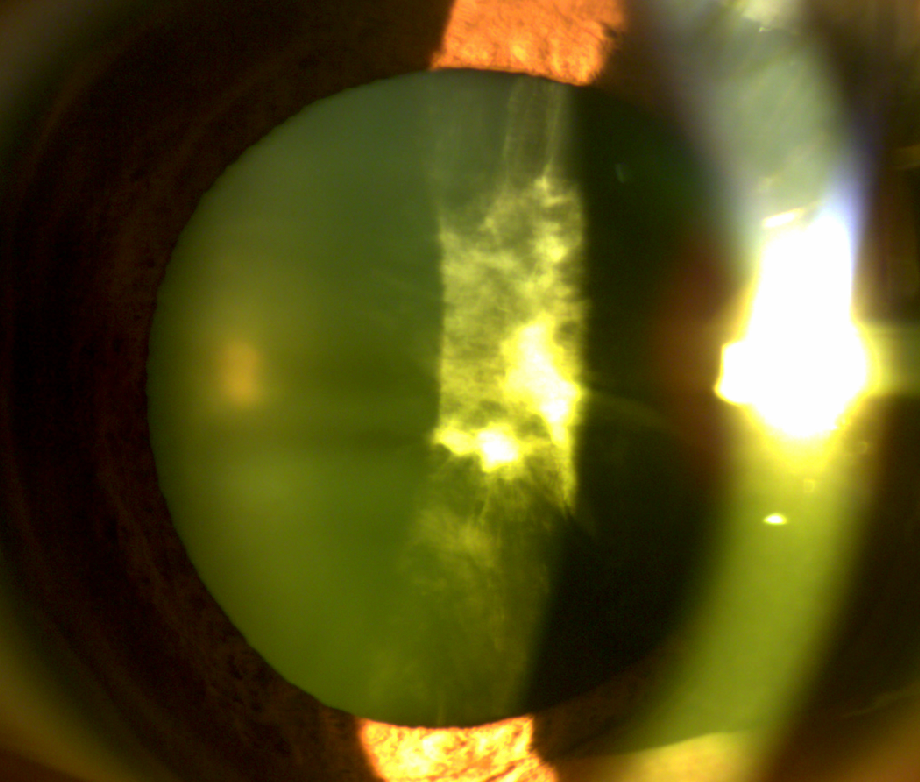

노안과 백내장은 중장년층에서 흔히 발생하는 시력 저하의 주요 원인입니다. 백내장은 수정체가 혼탁해지는 질환으로, 노화와 함께 진행되며 시력 장애를 유발할 수 있습니다. 하지만 현대 의학의 발전으로 백내장 수술이 효과적인 치료법으로 자리 잡았으며, 기능의학적 접근을 병행하면 회복을 극대화할 수 있습니다. 본 글에서는 백내장 수술 시 노안까지 교정하는 방법과 기능의학적 회복 전략을 상세히 다루겠습니다. 👀

2. 백내장 수술과 노안 교정

백내장 수술 시 노안 교정이 반드시 함께 이루어져야 합니다. 다양한 기능성 인공수정체(다초점, EDOF 등)는 수술 시에만 삽입할 수 있기 때문입니다. 따라서, 환자의 생활 패턴과 요구에 맞는 수정체 선택이 매우 중요합니다. ✅